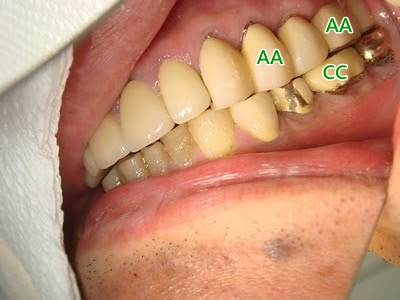

AA對應於下圖中CC (日前的牙根X光片 呈現蠻大的根叉腐穴) 牙齦已爆出膿包

BB乃AA半年以前的x光片,似乎根叉腐坑 沒有目前的大 (x光拍攝角度不是很相同 不算是很恰當的比對)

AA看起來似乎是健固潔淨的假牙 其實根叉腐穴暗藏膿炎 且長年清除不到。不斷的暗潛著無痛 無感覺 持續腐壞的根叉腐穴 逐漸漫延至牙根環周骨牆 終於爆膿。牙根地基變淺。

所以黏死的固定假牙 應盡早拆掉,診斷評估後 改設計成New Taiwan 根叉分切式Konus 就大有可能 免除牙根骨牆的繼續腐爛 才可長久地保住該牙,長保功能。

狀似健固 潔淨的黏死固定假牙 往往很高的百分比 暗藏深齦膿包或根叉 腐坑!

假牙設計成黏死的固定牙橋 此時的深肉隙 二叉 三叉牙根 腐坑 無法徹底治療 平常極困難保潔。日久終究會爆膿 無法根治 目前已有New Taiwan Konus分切牙根的牙周治療法+子內冠補綴法 與予安全 安心的解決這些問題。